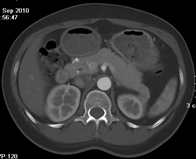

如上圖所示,相鄰的三張軸位圖像未見明顯異常,根據傳統軸位圖像很難得到準確的臨床診斷。

同一病人利用容積數據進行三維處理后,高品質MPR和三維圖像上則清晰顯示了縱向排列的腹腔干與腸系膜上動脈相鄰近,血管發生變 異,近端血管閉塞,為臨床提供了精確的診斷信息。